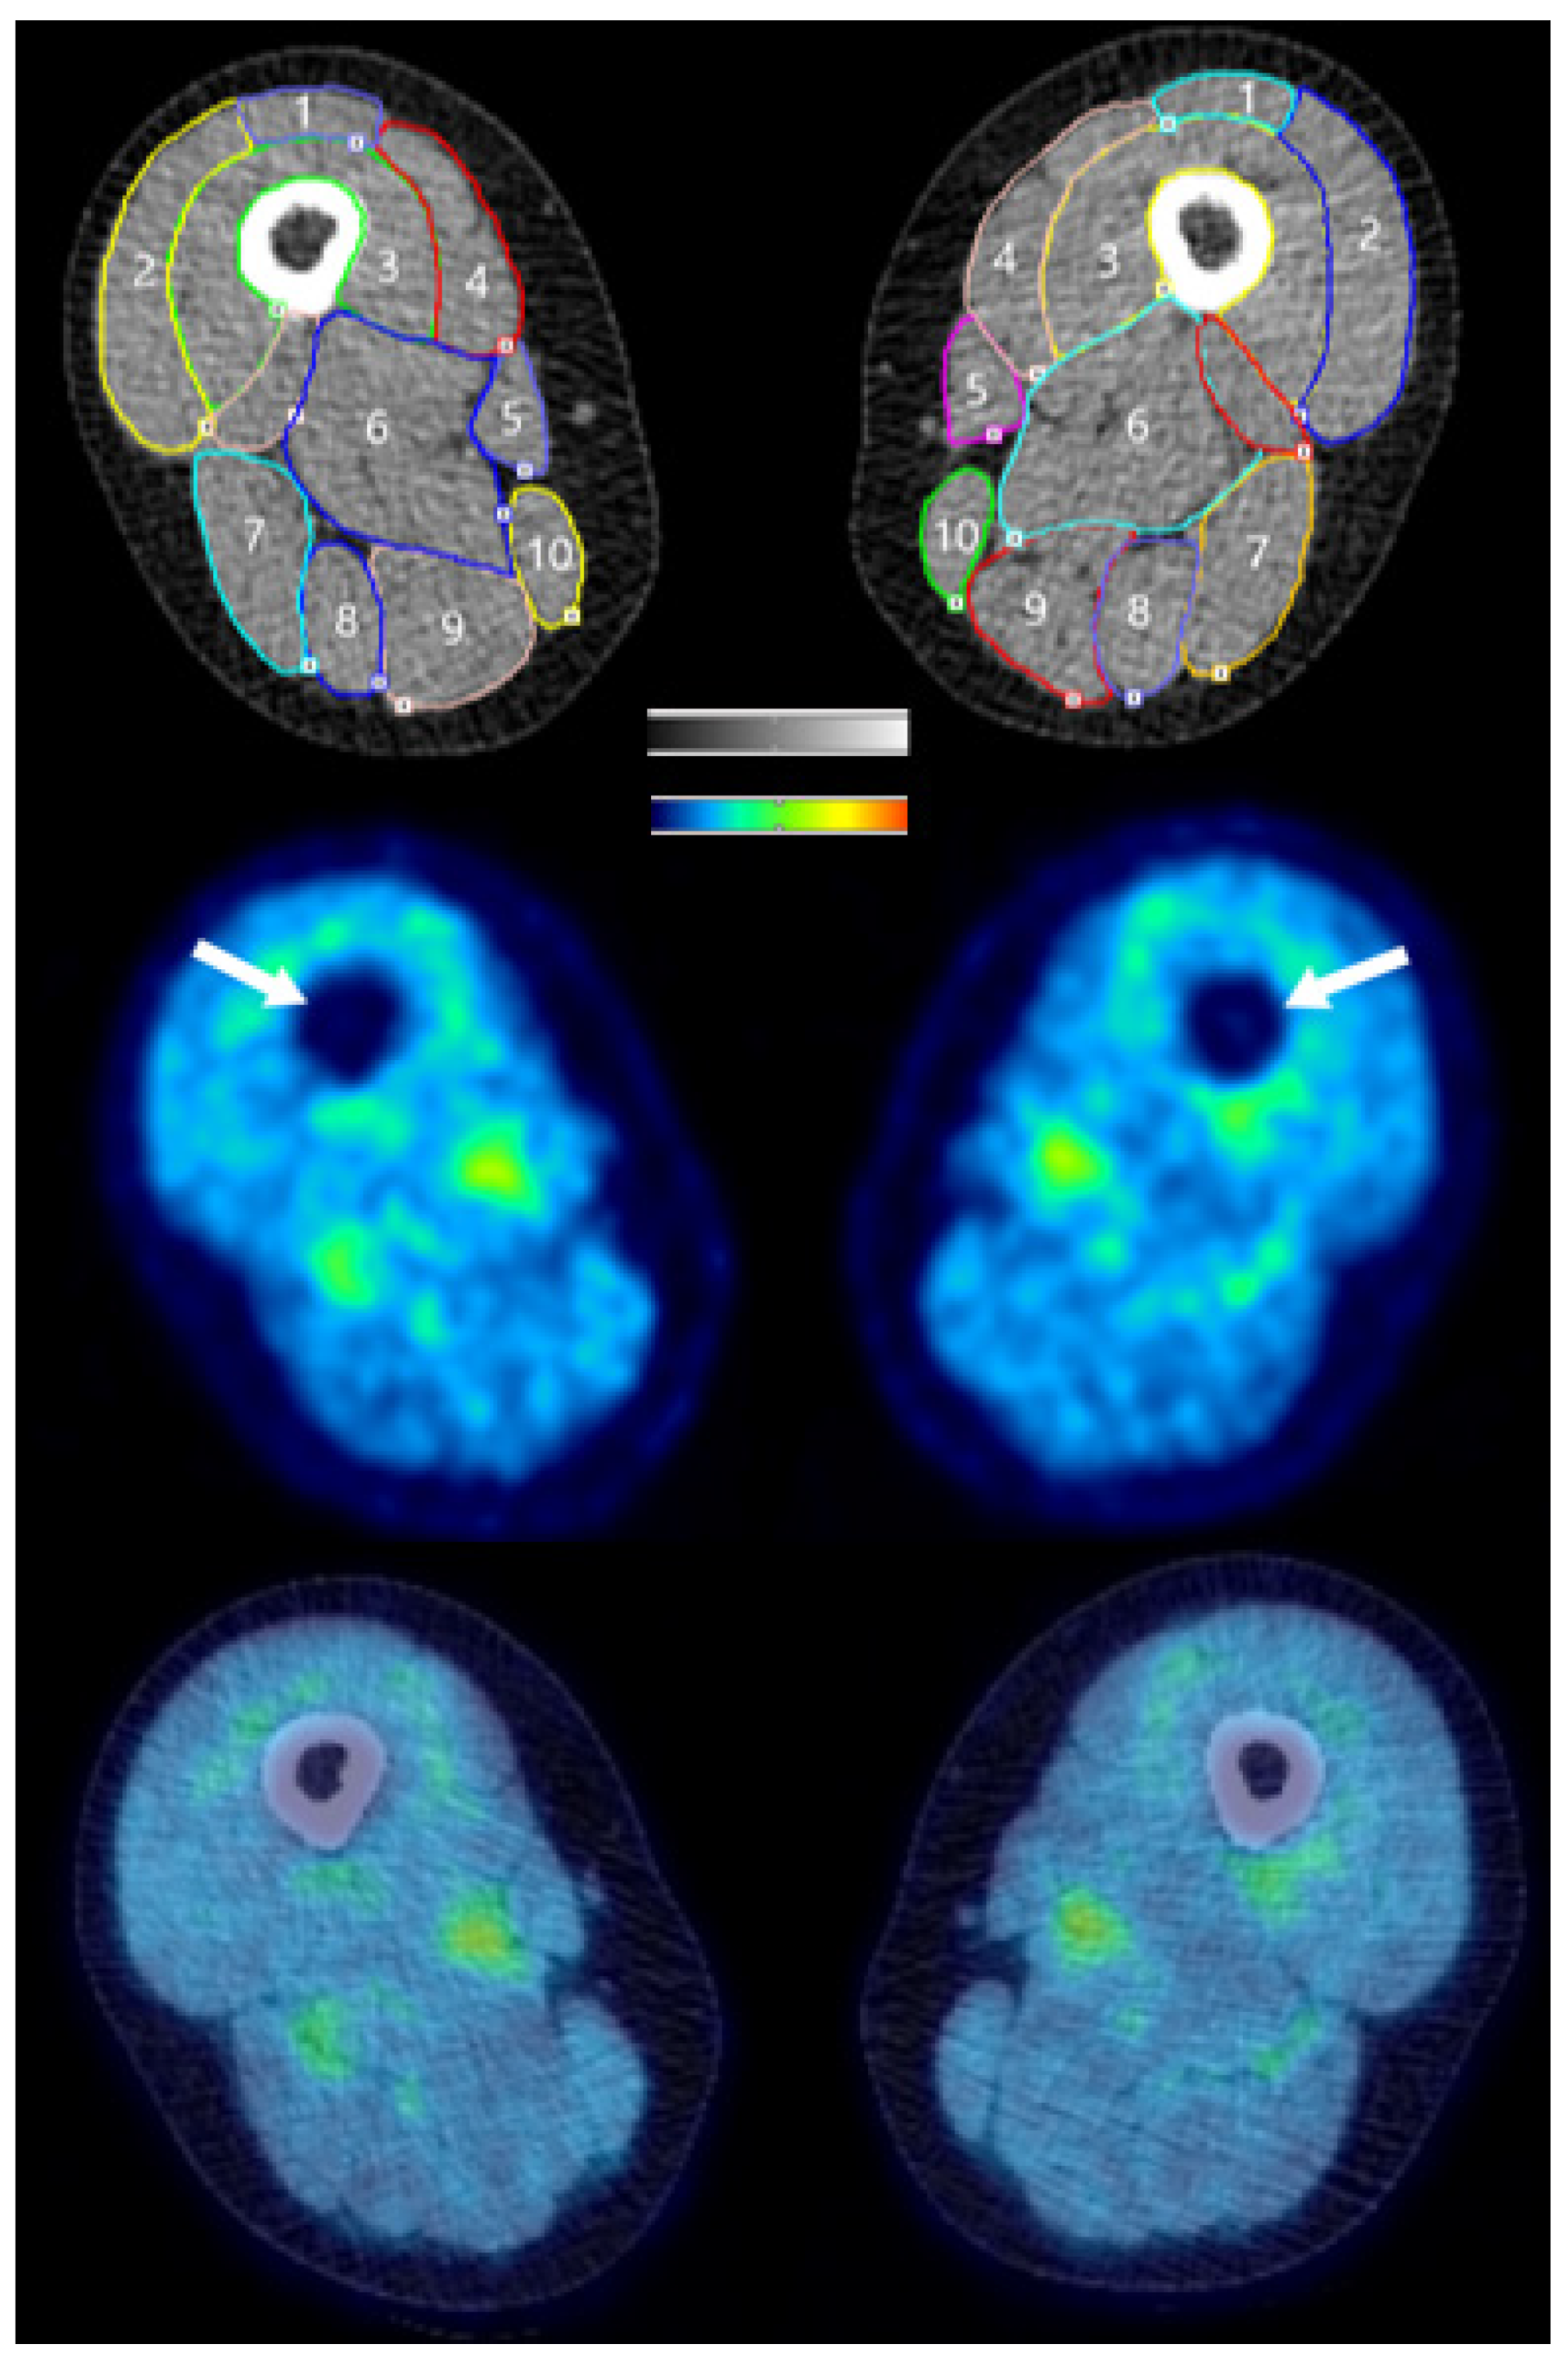

2.5. PET/CT Imaging